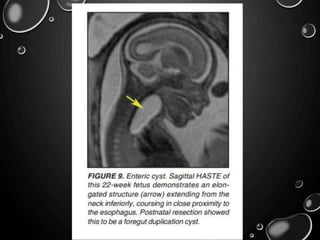

FOREGUT DUPLICATION CYSTS

• INTRATHORACIC- DIVIDED INTO BRONCHOGENIC, ESOPHAGEAL

DUPLICATION, AND NEUROENTERIC CYSTS.

• BRONCHOGENIC CYSTS REFLECT ABNORMAL BUDDING AND

DEVELOPMENT OF THE VENTRAL FOREGUT DURING THE FIRST

TRIMESTER OF GESTATION.

• ESOPHAGEAL OR ENTERIC DUPLICATION CYSTS RESULT FROM

MALDEVELOPMENT OF THE POSTERIOR DIVISION OF THE EMBRYONIC

FOREGUT .

• NEUROENTERIC CYSTS ARE FOUND IN THE POSTERIOR MEDIASTINUM

AND MAY COMMUNICATE WITH THE SPINAL CANAL, A CONDITION

OFTEN ASSOCIATED WITH UNDERLYING BONY ABNORMALITIES OF THE

SPINE.